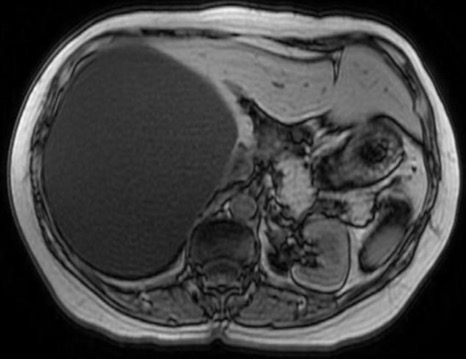

Aspetto RM

- Alterazione focale ben circoscritta, ipointensa in T1, iperintensa in T2 (isointensa al liquor), priva di enhancement post-contrastografico.

- Nelle sequenze colangiografiche non si riconosce una comunicazione con l’albero biliare.

- La cisti epatica a contenuto proteinaceo ha segnale iperintenso in T1.

- Nel caso di emorragia intracistica, il segnale sarà eterogeneo sia nelle sequenze T1 che T2, spesso con un livello fluido-fluido.